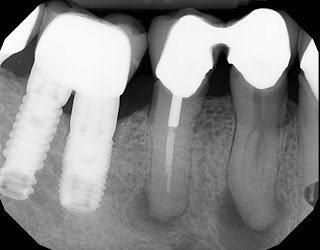

Untreated, you will see radiolucencies centered on the exit as in this #9 retreated below. I measured to the depth of the lateral canal and focused my irrigation and irrigant activation at that level.